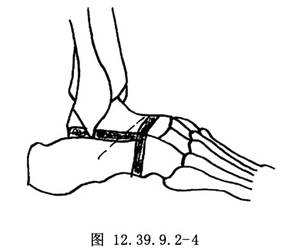

1.在足外侧沿皮肤皱褶做一斜行切口,切口中心位于跗骨窦表面,于后外侧距舟关节水平起自趾长伸肌腱的外侧缘(图12.39.9.2-4)。向后延长切口,弯向跖侧,止于腓骨肌腱水平。仔细保护伸肌腱与腓骨肌腱,沿切口经跗骨窦锐性切至趾短伸肌。将趾短伸肌起点连同跗骨窦内的脂肪一起翻向远侧,清除跗骨窦所有的残余软组织,显露距下、跟骰关节以及距舟关节的外侧部分。

3.找到跟骨的前关节突,沿跗骨窦底面水平将其切除,以便更好地显露所有关节。做此项截骨时,用骨刀平行足底面截骨,保留切下的骨以备植骨用。然后,用骨刀去除跟骰关节的关节面以显露松质骨。除非需要楔形切骨以矫正骨性畸形,否则一般在两侧去除等量的骨质(图12.39.9.2-4)。用直的和弧形骨刀去除距骨头远侧部分,显露距头松质骨的骨质即可。可插入小的椎板撑开器,以便获得更好的显露。可能需要在内侧另做一切口以显露距舟关节的最内侧部分。去除舟骨的近侧关节面和软骨下骨,修整其表面并使其变粗糙,以便与距骨紧密贴合(图12.39.9.2-5),切除载距突的关节面及距下关节的前关节面。